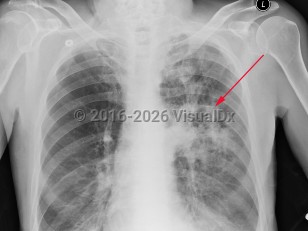

EVALI

COVID-19

Drug-induced pneumonitis